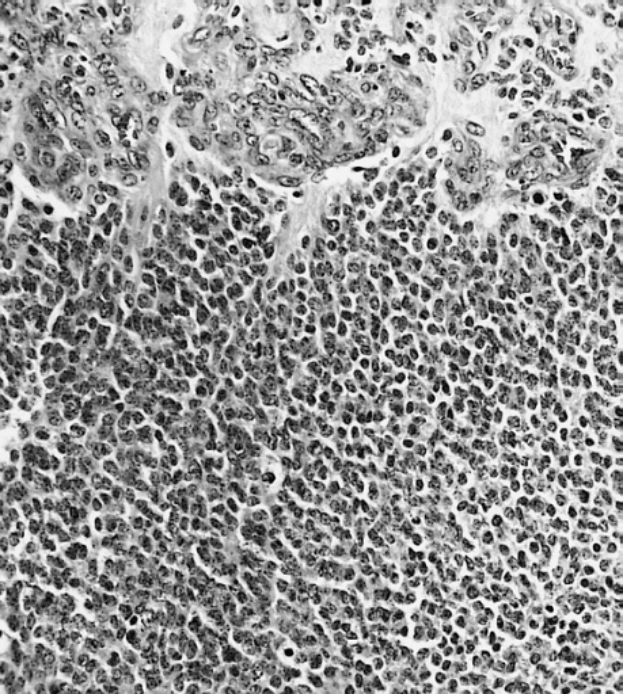

Ein schwarz-weißes Mikroskopiebild einer kleinen Zellgruppe, die mit Anti-PFA1-Antikörper und BSA gefärbt ist.Aurelia Aumann

Ein Start-up aus Hannover könnte die medizinische Diagnostik mit einer umweltfreundlichen Alternative zu Tierversuchen grundlegend verändern. Phaeosynt, gegründet von Forschenden der Leibniz Universität Hannover, hat ein Verfahren entwickelt, das Kieselalgen (Diatomeen) nutzt, um Antikörper für Tests herzustellen. Die Deutsche Bundesstiftung Umwelt (DBU) fördert das Projekt mit 125.000 Euro, um die Markteinführung voranzutreiben.

Der Ansatz von Phaeosynt ersetzt herkömmliche Tierzellen oder lebende Tiere in der Diagnostik. Durch den Einsatz von Antikörpern aus Kieselalgen spart das Unternehmen Ressourcen, Energie und Laborfläche im Vergleich zu klassischen Tierzellkulturen. Langfristig soll Tierversuche vollständig überflüssig machen – und damit nicht nur ethische Bedenken ausräumen, sondern auch Transportkosten senken.

Das Start-up hat bereits zwei Patente angemeldet und bereitet den Marktstart seines ersten Produkts vor: einen veganen Schwangerschaftstest ohne Tierversuche. Die Produktion erfolgt in Kooperation mit Senova, einem Hersteller von Biokunststoffen. Bis Ende 2026 plant Phaeosynt zudem die Markteinführung von drei weiteren Diagnostik-Tools, darunter Tests für Krebserkennungsmarker, schnelle Infektionsnachweise und die Bewertung von Herz-Kreislauf-Risiken.